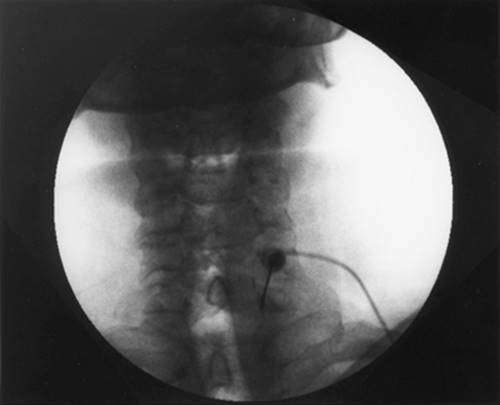

Approach and Technique: Fluoroscopy is used to take an anterior–posterior (AP) view and mark the T12-L1 junction (Fig. 63-4A). The beam is oblique to hide the ipsilateral transverse process (left side) behind the shadow of the upper third of the L1 vertebral body. A slight cephalad–caudad tilt of the beam may be necessary to square the endplates. This point should be marked and is approximately 6–8 cm from midline. After skin wheal and deep infiltration of local anesthetics, advance the needle parallel to the x-ray beam. Of great importance is taking frequent AP views to assess needle direction and lateral views (Fig. 63-4B) to assess depth. Once the anterior third of the vertebral body is reached, the stylet is removed from the needle and 0.1 cc–0.2 cc of PFNS is injected to occupy the needle and prevent air embolization. Once the aorta is pierced, very gentle aspiration is continuously applied until negative aspiration for blood. Advance 2–3 mm. Inject a small amount of the dye. Injection should be very slow and you should not feel any resistance. Resistance to injection may indicate injection in the wall of the aorta and may cause dissection. Injection of the local anesthetic should commence after desirable AP (Figs. 63-4D and E) and lateral (Figs. 63-4C and F) views are obtained with adequate propagation of the dye without intravascular runoff. Following the local anesthetic, absolute alcohol is injected slowly. Needle tip is about 1½ -2cm anterior to the vertebral body. The same is done on the right side, stopping just anterior to the vertebral body.

Figure 63-4. A: Needle position at T12-L1 AP view. B: Lateral view. C and F: Lateral view with contrast. D and E: AP view with contrast.